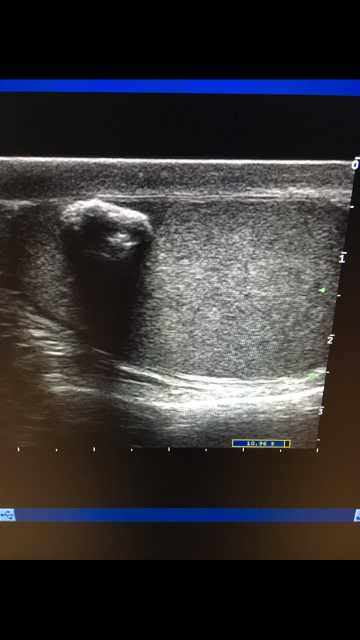

Образование в левом яичке

Выглядит обычным кальцификатом

Или кальцифицированная киста.

Возможно, но маловероятно, для кисты с кальцинированной стенкой больше характерен ровный контур и правильная форма

Согласен, это я покинул для диф.ряда.